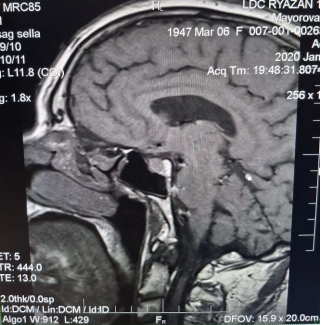

Анамнез заболевания: со слов сына (в сопровождении которого была на приеме), 29.01.2020 пациентка в связи с жалобами на головокружение и слабость самостоятельно прошла МРТ головного мозга (рис. 1, рис. 2, рис. 3).

Рис. 1. МРТ головного мозга (T1 sag sella)

Рис. 2. МРТ головного мозга (T2 Cor)